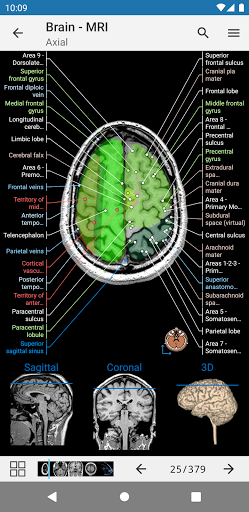

-New module: Anatomical atlas of the lumbar spine on a CT, intervertebral discs and lumbosacral hinge in axial, coronal, and sagittal sections, and on 3D images-German is now supported for anatomical structures-Updated search mode (two new buttons in details view of a structure and a close button next to the searched structure label)-Fix search error on some Android versions-Fixed small bugs

-New module: Anatomical atlas of the lumbar spine on a CT, intervertebral discs and lumbosacral hinge in axial, coronal, and sagittal sections, and on 3D images-German is now supported for anatomical structures-Updated search mode (two new buttons in details view of a structure and a close button next to the searched structure label)-Fixed small bugs

-Two new modules : Brain - TOF and Brain Angiography, Atlas of normal neurovascular anatomy of arteries of the brain on a cerebral angiogaphy.-The interface has been reworked.-A new tab named "QuickLinks" is available, dispatching modules in sections of the human body and allowing you to fast travel to the modules you are looking for.-Fixed small bugs.